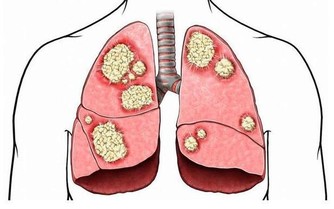

血腥味的屁,很有可能是消化道有出血。血液積聚在患者胃腸道中,胃酸及腸道細菌把血液分解,有時排出的糞便會像柏油一般,屁也會有腥臭味。此外,腸道有惡性腫瘤時,因癌組織糜爛、剝落、出血,再加上細菌的分解發酵作用,放的屁也有腥臭味。